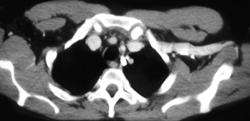

Neurogenic Tumor Invades the Heart